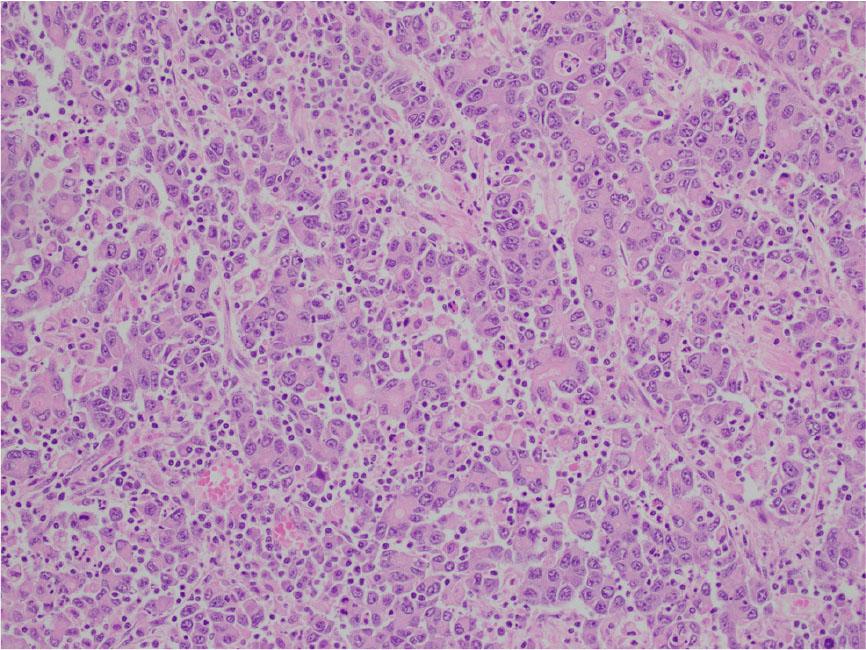

Figure 2: